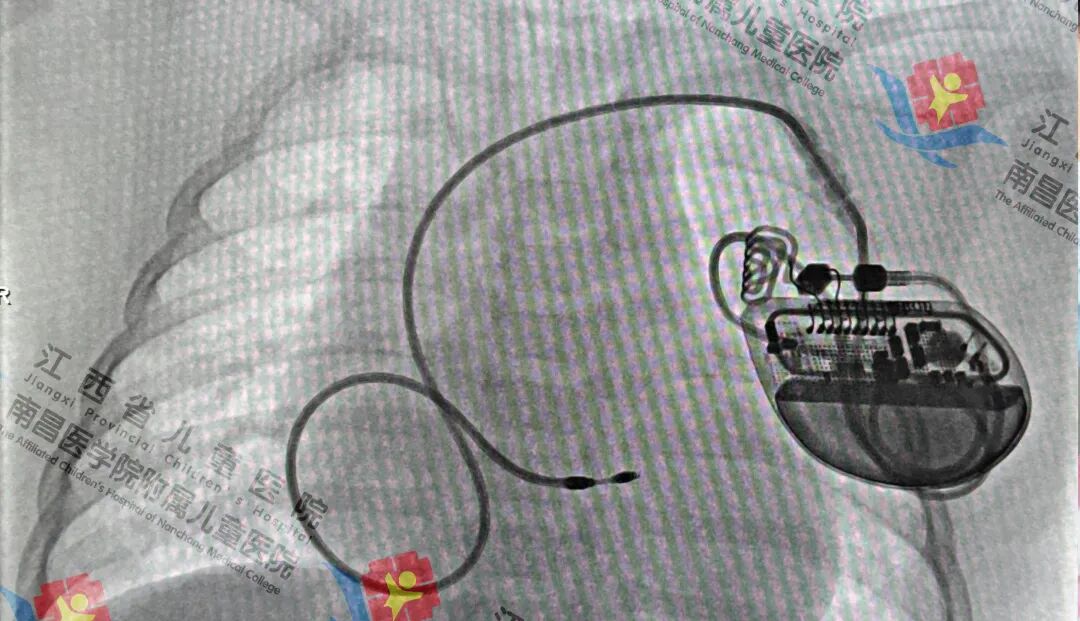

术后图术后,起搏器立即开始工作,乐乐心率恢复至正常范围,血流动力学显著改善,在没有静脉药物提升心率的情况下也无抽搐再发生。目前恢复情况良好,已出院。周云国介绍,严重的心动过缓会导致患儿乏力、眩晕、活动耐量下降,甚至发生晕厥和猝死。若孩子出现相关症状,应尽早到医院就诊,明确诊断并及时干预。

随后,周云国团队将一台体积微小、性能先进的起搏器发生器埋藏于患儿左侧胸大肌下的皮下“口袋”内(该位置既避开了骨骼发育关键区,又能减少对日常活动的影响),手术进展顺利。

术中,在心血管内科主任许飞的带领下,周云国团队借助影像设备的精准引导,为乐乐的心脏先搭建了“人工电路”,将细细的起搏电极通过血管顺利送达乐乐心腔内的最佳位置。周云国团队并未急于固定,而是反复调试电极位置,通过专业仪器监测起搏阈值(即起搏器带动心脏跳动所需的最小电量)与信号感知能力,最终锁定了“阈值最优、感知灵敏”的固定点,既保证了起搏效果,又最大程度降低了心脏损伤风险。